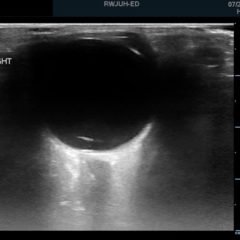

Bedside echocardiogram was performed, which revealed a free-floating thrombus in the right atrium on the sub-xiphoid view as seen in the video. The right atrium is denoted by the blue circle, in which a hyperechoic mobile mass can be seen. This finding was confirmed by an official echocardiogram which shows the thrombus in the right atrium extending through the tricuspid valve, as shown in the second image denoted by the red arrow. Significant right heart strain was also found, with severe pulmonary hypertension and intraventricular septal flattening.

Right atrial thrombus is a rare finding that is almost exclusively found complicating pulmonary thromboembolism1 and carries a high mortality rate from 27%1 to 44%.2 Typically the diagnosis is made via echocardiogram, with the sub-xiphoid view most likely to provide adequate views of the right atrium. The sub-xiphoid view is obtained by using the left lobe of the liver as an acoustic window, with the probe angled cephalad toward the thorax. Treatment strategies for right atrial thrombus include anticoagulation, surgical thrombectomy, or thrombolytic therapy. At this time there are no evidenced-based guidelines to direct treatment strategy; however, the largest retrospective analysis shows significantly increased survival with thrombolysis, having a mortality rate of 11.3%, in comparison to 28.6% with anticoagulation and 23.8% with surgical thrombectomy.3 Another study reports that hypotension and pulmonary embolism severity predicts mortality risk in the setting of right heart thrombi, but not the size, shape, or mobility of the thrombus on echocardiogram.4